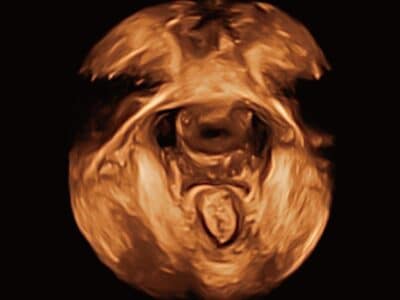

Automatický obličej

3D vizualizace obličeje plodu je důležitá pro diagnostiku obličejových anomálií.

Odstranění okluzí a objektů lze snadno provést pomocí funkce Auto Face, abyste získali optimální zobrazení obličeje plodu.